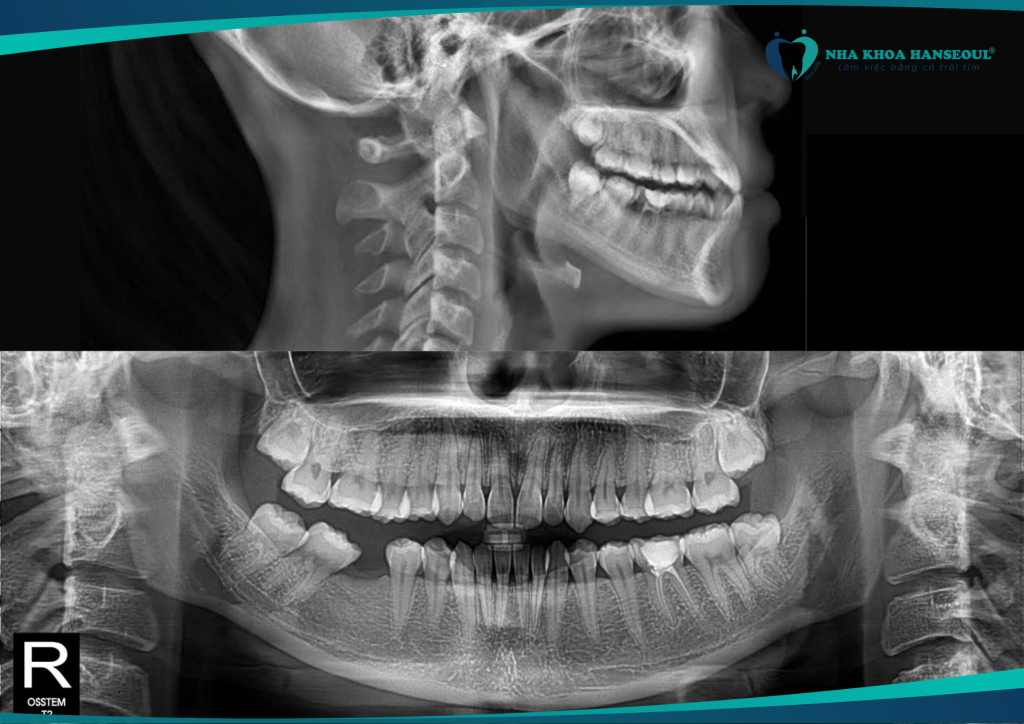

Trước khi đến với Hanseoul, Thanh Thủy gặp phải nhiều vấn đề răng miệng:

- Sâu răng mặt nhai ở răng số 17 và 27

- Mất răng số 46

- Vôi răng cấp độ 2

- Khớp cắn ngược, ảnh hưởng đến thẩm mỹ khuôn mặt và chức năng ăn nhai